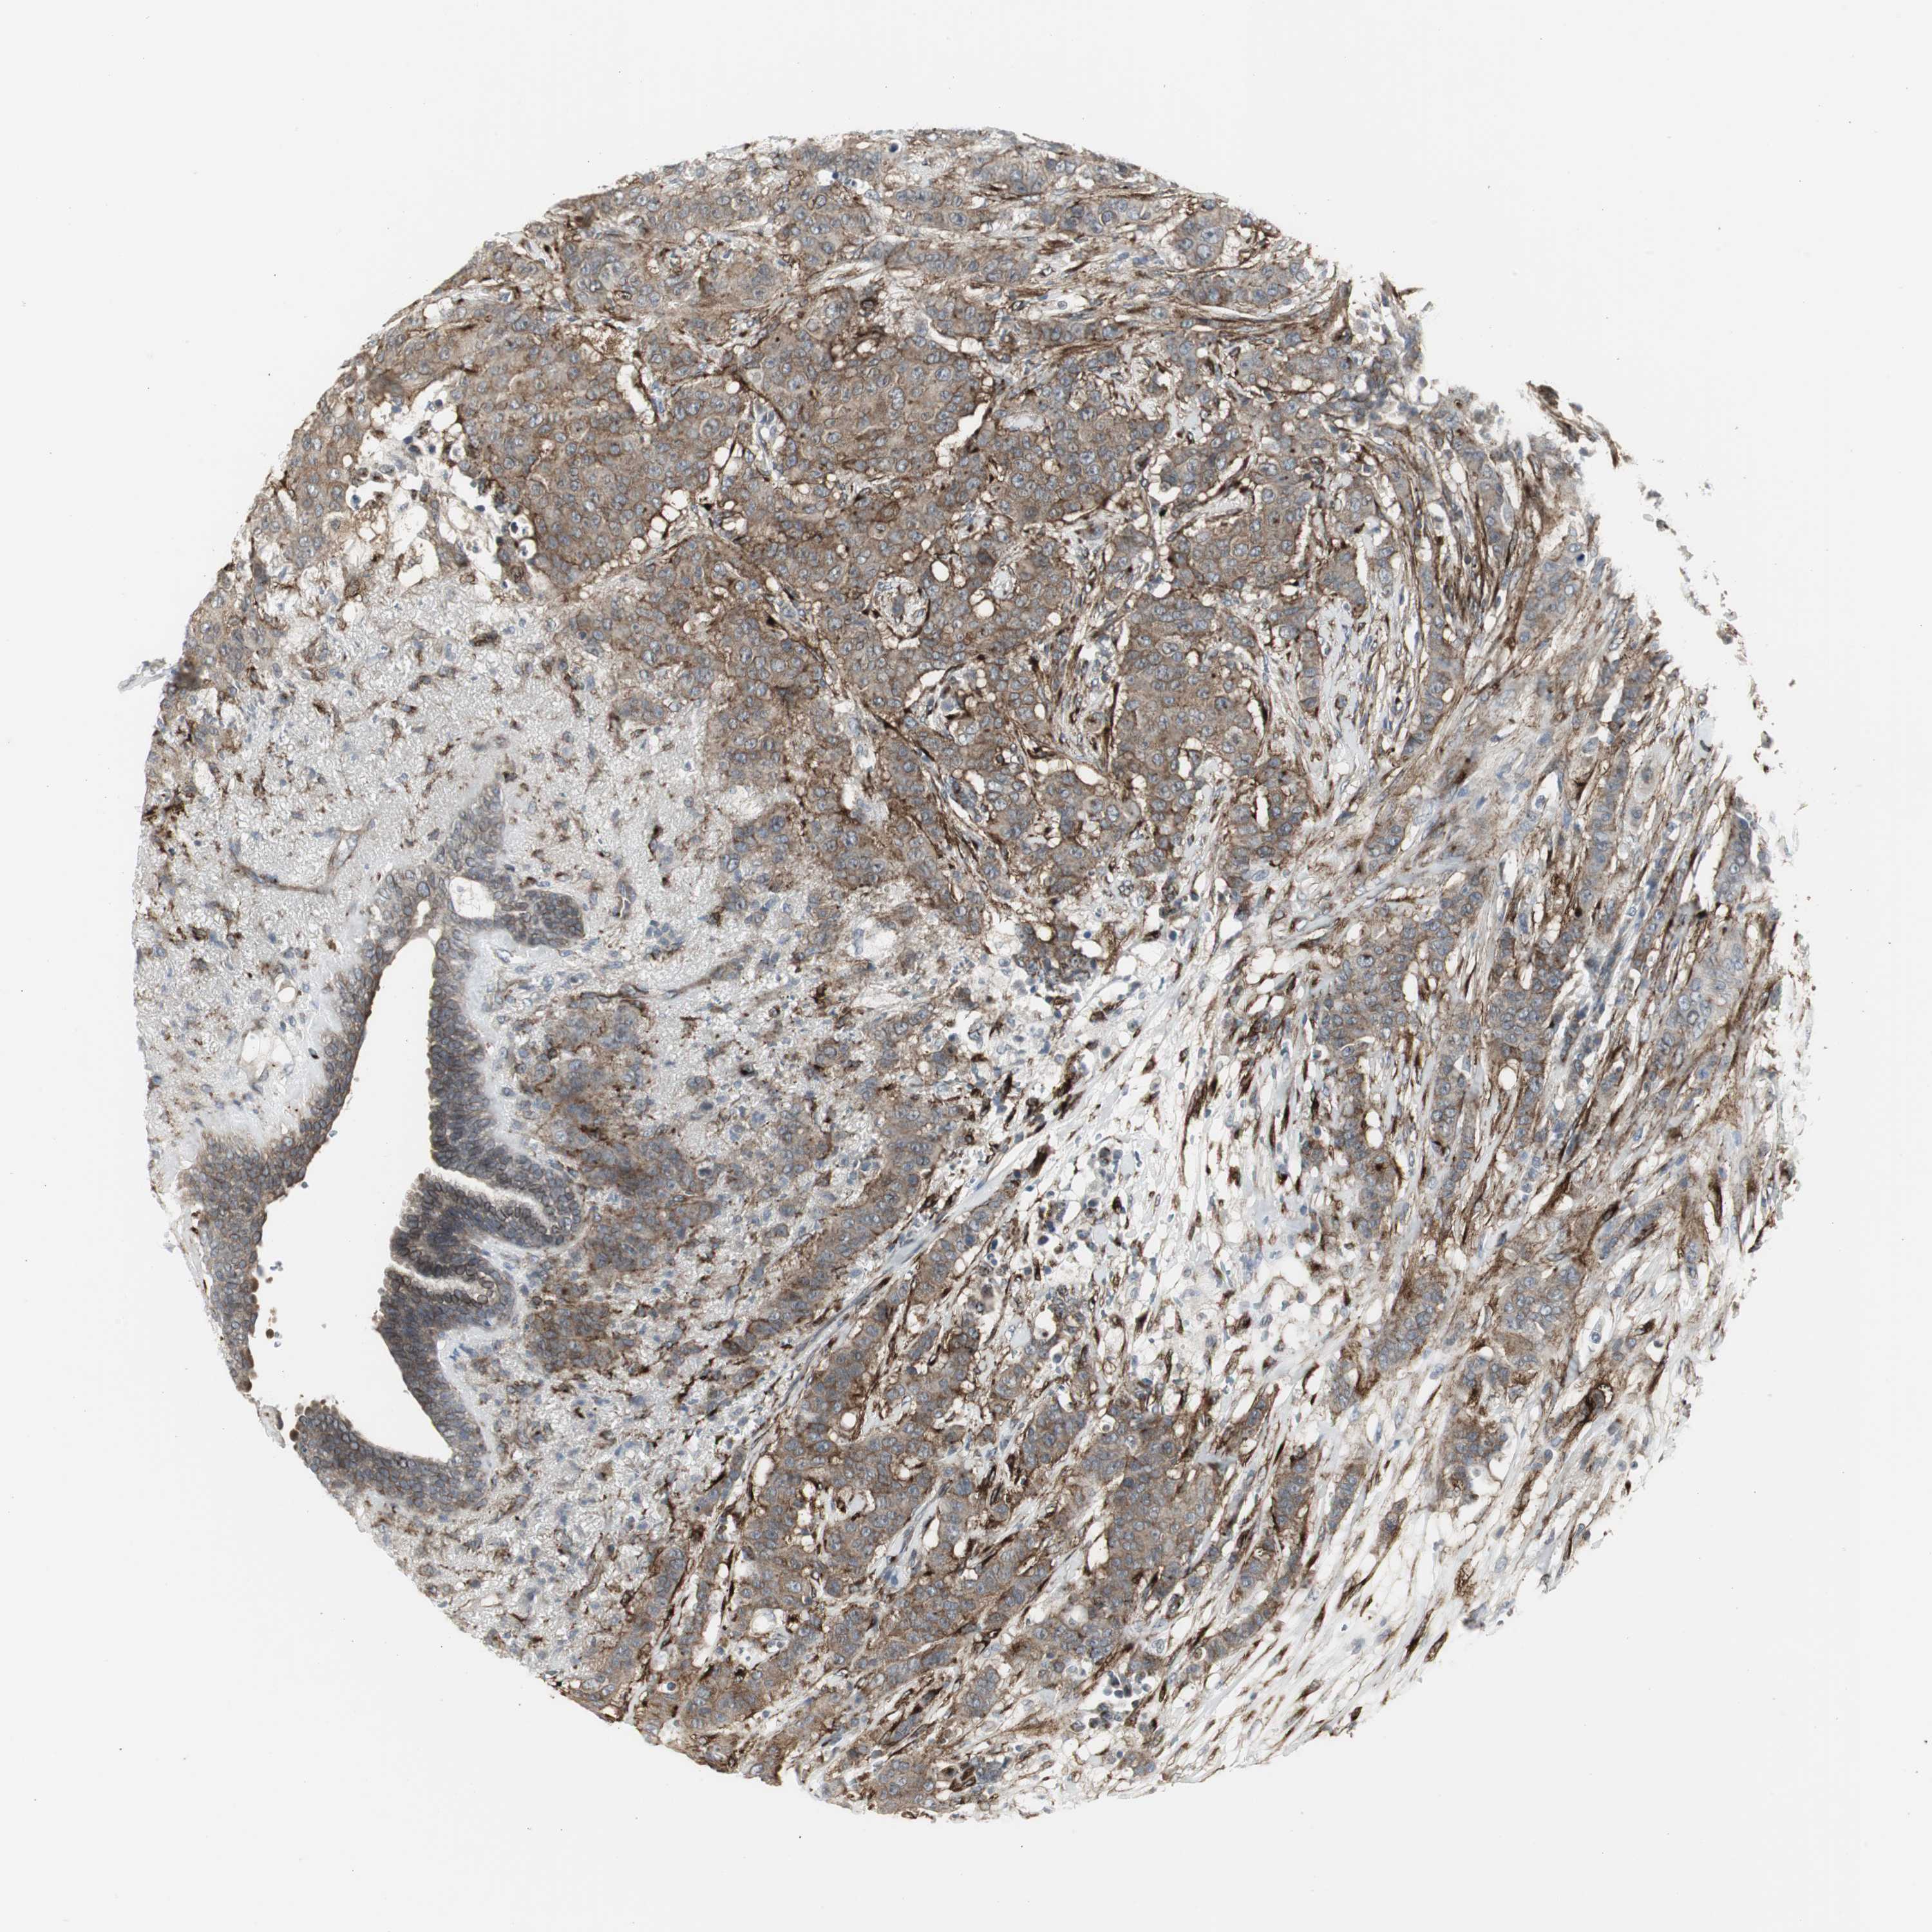

BRCA TCGA BRCA VALIDATION PROTEIN EXPRESSION

ANTIBODIES

AND

VALIDATION